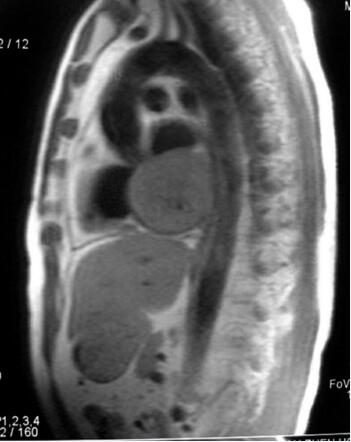

肾上腺CT未见异常;UCG未见心脏肿瘤;MIBG未见嗜铬细胞瘤征象;奥曲肽显像提示心脏内放射性浓聚区;再次复查UCG提示主动脉起始部前壁直径cm左右肿物,突出于右室流出道;CT示主动脉前壁肿瘤,与周围结构分界不清图31-1);MR(T2像)示主动脉前壁肿瘤,与周围结构分界不清(图31-2);冠状动脉造影(RCA)示右冠状动脉近段被肿物压迫闭塞,可见肿物血管影。

图31-1 CT示主动脉前壁肿瘤

术中所见:术中见肿瘤位于主动脉根部前壁,与主肺动脉根部、右室流出道粘连紧密,3cm×4cm大小(图31-3)。右冠状动脉细小。沿肿瘤包膜外切除肿瘤。行右冠状动脉近段结扎,将右冠状动脉肿瘤供血部分切除。以人工血管内衬自体心包修补主动脉,自体心包片修补主肺动脉前壁。

MRI和CT对明确和证实心脏嗜铬细胞瘤并了解其形状特点、周围浸润方面有重要价值,CT要求为高速增强CT,而慢速CT不能适应心脏处于快速运动中的特点,亦难以捕捉肿瘤与心脏腔室增强剂摄取差异的短暂时刻。与CT相比,MRI对软组织有更高的分辨率和敏感性,嗜铬细胞瘤MRI在T2像中呈高信号,而心脏血流在T2像中呈低信号,因而MRI诊断心脏嗜铬细胞瘤较CT扫描更具优势。超声心动图对发现心脏嗜铬细胞瘤意义值得研究,文献报道普通超声心动图和经食道超声心动图对心脏嗜铬细胞瘤均有很高的检出率(4/5和7/7),并总结出其特征为“位于房室间沟邻近心外膜冠状动脉的卵圆形、颗粒状肿瘤”,将经食道超声列为最有效的检出手段之一。冠脉造影有利于明确肿瘤血供情况,指导手术设计及术前准备,但操作风险大,宜作充分准备。